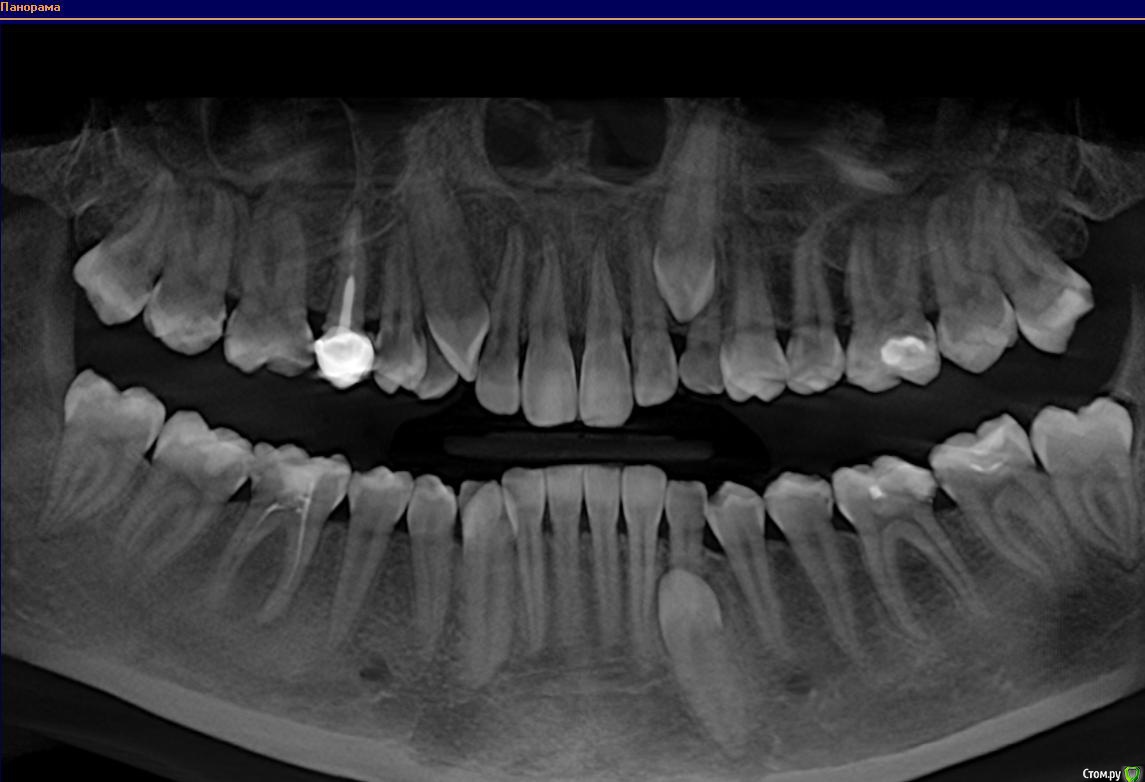

Ксения_ Опубликовано 27 августа, 2015 Поделиться Опубликовано 27 августа, 2015 (изменено) Здравствуйте Уважаемые Доктора! КТ сделано 4 мес назад. После этого пролечен кариес 14, 16, 37, 35. Пролечен пульпит 25, 36.Осталось пролечить пульпит в 15, 26, 47. Удалить все восьмерки.Далее ортодонтия. Стоит вопрос об удалении 46. Зуб ранее был пролечен другим врачом некачественно (+ пропущен канал).Мой лечащий доктор, после консультаций с коллегами, предлагает удаление, т.к. с его слов прогноз у этого зуба неблагоприятный (считает, что через пару лет процесс повторится) и смысла в столь дорогом лечении нет. Мне, конечно, хотелось бы по возможности зуб сохранить.Как вы считаете какой прогноз у этого зуба? P.S. Зуб не беспокоит. Точнее ни один зуб у меня вообще ни разу в жизни не болел (несмотря на такое количество пульпитов, которые для меня были неожиданностью. Врачу своему доверяю.). Несколько докторов которые меня смотрели считают, что у меня высокий болевой порог. Изменено 27 августа, 2015 пользователем Ксения_ Ссылка на комментарий

M@estro Опубликовано 27 августа, 2015 Поделиться Опубликовано 27 августа, 2015 (изменено) Судя по рентгену - прогноз благоприятный. Зуб сохранен,это главное. "процесс повторится" - на это при современном подходе выделяют не более 5 % .Если бы у меня 95 % вероятности в казино было - я бы дом поставил , не то что зуб полечил ) Ключевое при перелечивании - соблюдение современного протокола лечения. P.s. После лечения уже больше двух лет прошло,недавно был на осмотре - процесс все никак не повторится )) Изменено 27 августа, 2015 пользователем M@estro 3 Ссылка на комментарий